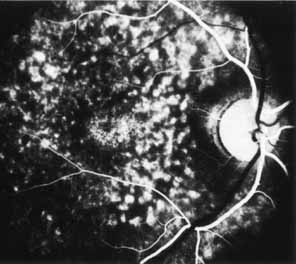

Although there is no reported genetic heterogeneity, there is wide phenotypic variation within the disorder. The major finding within the macula is a classic radial cystic maculopathy. Although retinal signs have been described in infants as young as 3 months, foveal schisis may be difficult to detect, leading to underdiagnosis. The diagnosis is usually not made until the affected male reaches school age (4 to 8 years of age) and encounters visual problems secondary to foveal involvement. Typical foveal schisis findings have been reported in 68% to 100% of eyes within various series.37,38 Foveal schisis is the only finding in about half the cases. It is characterized by the presence of radiate perifoveal microcysts located in the nerve fiber layer (Fig. 1) with radiate plications of the overlying internal limiting membrane that are seen especially well on monochromatic (red-free) photography (Fig. 2). The microcystoid change may slowly progress to form a macular cyst or hole. Foveal schisis has been reported in association with Goldmann-Favre vitreotapetoretinal dystrophy and rarely may be seen in rod-cone dystrophy or as an autosomal dominant or recessive condition.39–43